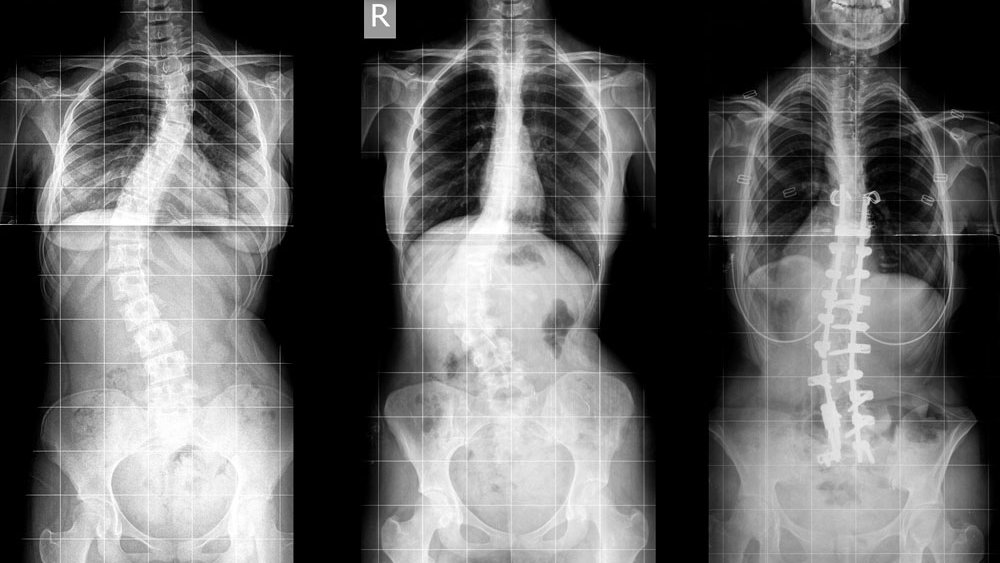

Сколиоз 19 Градусов Фото

Сколиоз 19 Градусов Фото 130 фото